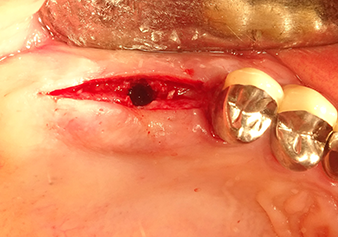

Preoperative findings: The alveolar ridge has healed well, including sufficiently broad, keratinised gingiva

Fig.1: Preoperative findings: The alveolar ridge has healed well, including sufficiently broad, keratinised gingiva.

Following atraumatic preparation of the mucoperiosteal flap, the implant position was marked with the I1 instrument and the site prepared – until initial resistance was felt. Piezosurgical instruments were used in an up and down movement without any pressure being exerted. The piezoelectric vibration produced the desired and efficient cavitation.